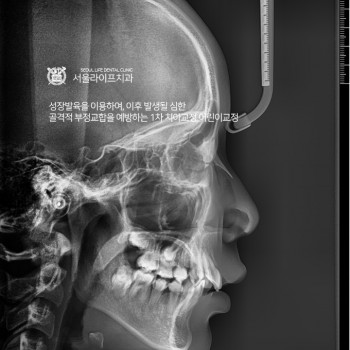

어린이 치아교정 및 청소년교정 - 1차교정

의학박사 김신근원장

보건복지부인증 구강악안면외과전문의